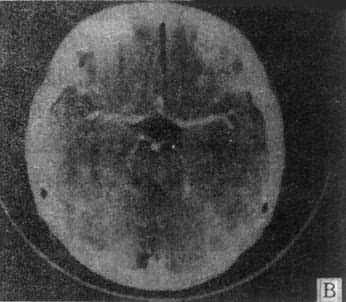

10mm底颅层面 此层面通过眦耳线上方10mm,由前向后可见眼眶上部、蝶窦和中颅凹底、枕骨及枕大孔等颅底结核。20mm蝶鞍层面 可见垂体、四脑室、桥池和桥小脑角池、岩锥与内耳道、前、中和后颅凹脑组织结构。本层面重点观察垂体和后颅凹结构。(图5-1-4A)。30mm鞍上池层面 可见鞍上池呈六角星或五角星形低密度脑脊液间隙,增强CT扫描尚可见脑底动脉环在池内的分布情形(图5-1-4B)。鞍上池后方、环池和四叠体池包绕部分即为中脑。40mm三脑室前部层面 重点观察内囊、基底节和丘脑区(图5-1-4C)。50mm三脑室后部层面除显示内囊、基底节和丘脑区外,同时是观察三脑室后部松果体区重点扫描层面(图5-1-4D)。60mm侧脑室体层面可观察侧脑室体部、三角区和后角(图5-1-4E);增强CT尚可见直窦、上矢状窦和大脑镰强化显影。70mm侧脑室顶层面 可见侧脑室顶部、大脑纵裂、脑皮质和脑髓质(图5-1-4F)。80~100mm脑室上层面 脑皮、髓质、脑沟和大脑纵裂清楚显示。

图5-1-4 正常头部CT扫描

C、第三脑室前部层面 D、第三脑室后部层面

E、侧脑室体部层面 F、侧脑室顶层面